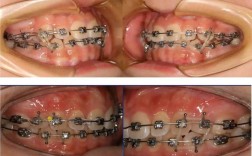

- 原理: 平面导板是一个由树脂制成的平板,通常粘固在上颌前牙的舌侧(有时也用于下颌),当患者咬合时,后牙无法接触,只有前牙咬在导板的平面上。

(图片来源网络,侵删) -